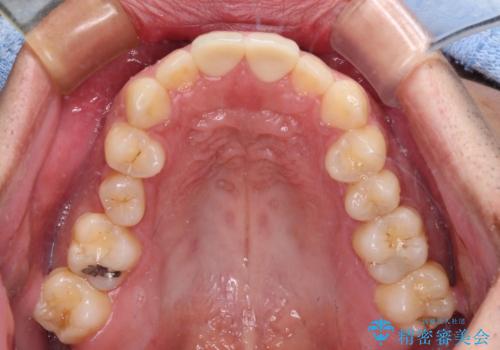

- 競技用自転車を運転中に転倒して前歯を強くぶつけ、欠けてしまったとのことで来院された患者様です。

近医にて欠けて部分を樹脂で修復してもらったものの、舌での感触が悪く、しみる感覚があるため、オールセラミッククラウンによる補綴治療を希望されていました。

仮歯に置き換え、しみる感覚が改善されてことを確認された後に、オールセラミッククラウンにて補綴治療を行うこととしました。